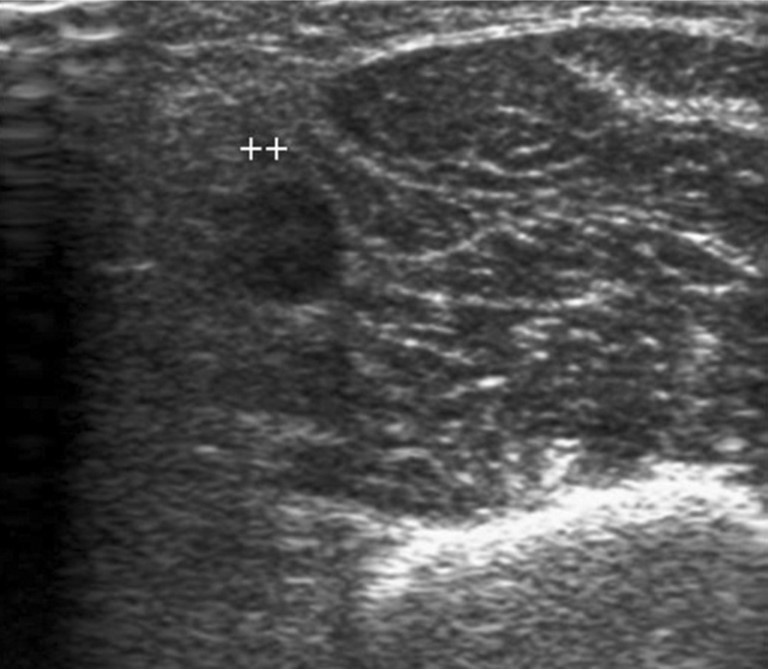

Initial shuntogram 상 total stenotic occlusion된 antecubital vein과 cephalic & basilic veins이 확인되었다(Fig. 1) 투시하에서 더 이상의 outflow vein을 확인할 수 없었으며 초음파상 1mm 크기에 가까운 흔적으로 확인되었다(Fig. 2). 7Fr, 24cm sheath(Accu-Sheath, Sung wonmedical, Korea, Cheongju) 로 폐색된 앞부위까지 전진시킨 후, 투시를 보조수단으로 하며 초음파를 main 유도 기구로 사용하여 real time으로 초음파 probe를 0.035’ J-tip & straight-tip guide wires(Terumo, Tokyo, Japan)와 5 Fr Kumpe catheter(Soft-Vu, AngioDynamics, USA, NY) 바로 위에 위치 시키면서 wire를 전진시켰다(Fig. 3). 시술 중 guide wire 가 혈관 외부로 뚫고 나가며 parenchymal injury를 유발하였다(Fig. 4A, B). 그 후 venous true lumen을 찾 angioplasty를 시행하였다(Fig. 5). 마지막 shuntogram 상 더 이상의 혈관 손상이 없이 재개통된 것을 확인하고 시술을 종료하였다(Fig. 6).

Fig. 2.

Sonogram at antecutibal vein